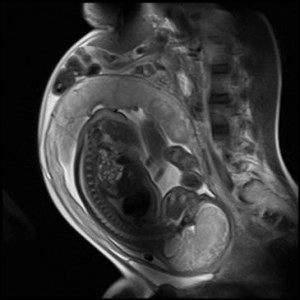

МРТ при беременности

В случае невозможности достоверно определить патологические изменения в организме матери или плода врач может принять решение о назначении МРТ при беременности.

Однако риск неблагоприятного влияния в первом триместре вынашивания, когда формируются основные системы и органы будущего ребенка, чересчур высок, поэтому исследование обычно проводят во время второго либо третьего триместра.

На текущий момент нет никаких фактов, говорящих о возможности осложнений развития плода из-за процедуры. Тем не менее, врачи предпочитают избегать даже теоретически возможных рисков и принимают решение о необходимости магнитно-резонансной томографии лишь при условии, если присутствует серьезная угроза здоровью женщины.

МРТ беременным женщинам проводят точно так же, как и всем прочим пациентам.

Как правило, МРТ беременным назначают в тех случаях, когда существует серьезная угроза жизни или здоровью матери и плода, причем другие способы диагностики, в том числе УЗИ, не дают точной картины патологических изменений. Показаниями к проведению процедуры служат:

Наиболее частой причиной назначения магнитно-резонансной томографии становится подозрение на патологию развития плода. Исследование необходимо, чтобы женщина могла принять осознанное решение либо о прерывании беременности, либо о лечении ребенка после его появления на свет.